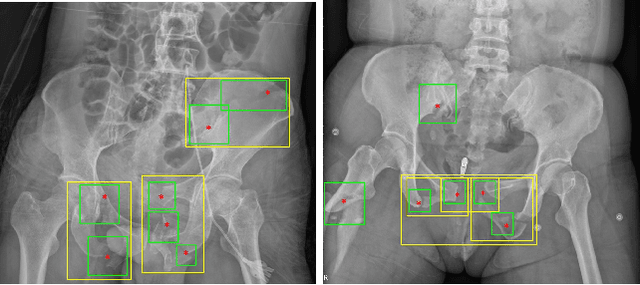

Abstract:Object detection methods are widely adopted for computer-aided diagnosis using medical images. Anomalous findings are usually treated as objects that are described by bounding boxes. Yet, many pathological findings, e.g., bone fractures, cannot be clearly defined by bounding boxes, owing to considerable instance, shape and boundary ambiguities. This makes bounding box annotations, and their associated losses, highly ill-suited. In this work, we propose a new bone fracture detection method for X-ray images, based on a labor effective and flexible annotation scheme suitable for abnormal findings with no clear object-level spatial extents or boundaries. Our method employs a simple, intuitive, and informative point-based annotation protocol to mark localized pathology information. To address the uncertainty in the fracture scales annotated via point(s), we convert the annotations into pixel-wise supervision that uses lower and upper bounds with positive, negative, and uncertain regions. A novel Window Loss is subsequently proposed to only penalize the predictions outside of the uncertain regions. Our method has been extensively evaluated on 4410 pelvic X-ray images of unique patients. Experiments demonstrate that our method outperforms previous state-of-the-art image classification and object detection baselines by healthy margins, with an AUROC of 0.983 and FROC score of 89.6%.

Abstract:Visual cues of enforcing bilaterally symmetric anatomies as normal findings are widely used in clinical practice to disambiguate subtle abnormalities from medical images. So far, inadequate research attention has been received on effectively emulating this practice in CAD methods. In this work, we exploit semantic anatomical symmetry or asymmetry analysis in a complex CAD scenario, i.e., anterior pelvic fracture detection in trauma PXRs, where semantically pathological (refer to as fracture) and non-pathological (e.g., pose) asymmetries both occur. Visually subtle yet pathologically critical fracture sites can be missed even by experienced clinicians, when limited diagnosis time is permitted in emergency care. We propose a novel fracture detection framework that builds upon a Siamese network enhanced with a spatial transformer layer to holistically analyze symmetric image features. Image features are spatially formatted to encode bilaterally symmetric anatomies. A new contrastive feature learning component in our Siamese network is designed to optimize the deep image features being more salient corresponding to the underlying semantic asymmetries (caused by pelvic fracture occurrences). Our proposed method have been extensively evaluated on 2,359 PXRs from unique patients (the largest study to-date), and report an area under ROC curve score of 0.9771. This is the highest among state-of-the-art fracture detection methods, with improved clinical indications.